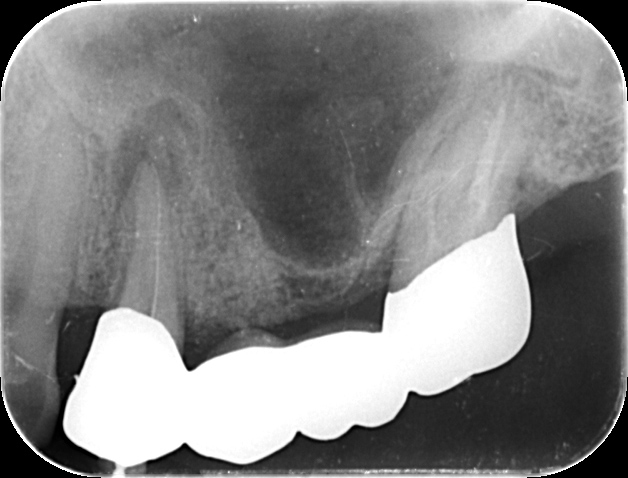

根管治療を行った歯に炎症が再発すると、歯の根の周囲に膿が溜まることがあります。このような症状では、通常の根管治療では対応できず、抜歯が必要になることもあります。

当院では、このような場合に「歯根端切除術」を用いて治療を行います。歯根端切除術は、歯茎を切開して炎症を起こした歯の根の先端と膿の袋をまとめて取り除く手術です。取り除いた後の空洞は血液で満たされ、時間の経過とともに骨が再生します。

一般的には、奥歯に対する歯根端切除術は難しいとされています。しかし、当院では問題のある歯を一度抜歯し、治療を行った後に元の位置に戻す「再植」という術式を用いることで、奥歯にも対応できる場合があります。